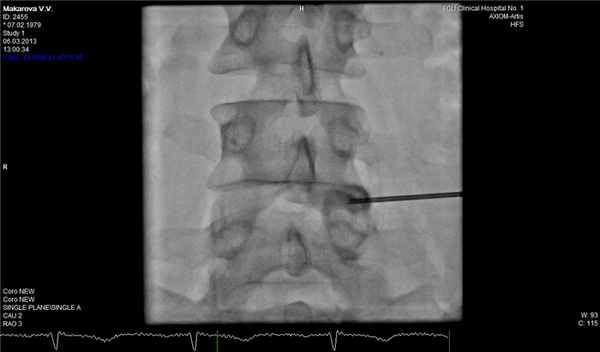

В трудных для диагностики случаях можно дополнительно к МРТ позвоночника применить дискографию, которая достоверно подтвердит или опровергнет диагноз рецидивной грыжи диска. Эпидурография также может быть полезна для оценки состояния корешка в позвоночном канале.

![]()

Фораминальная рецидивная грыжа 5 мм. Дискография.

Сдавление корешка L4 в корешковом канале, несмотря на малые размеры грыжи. Эпидурография.